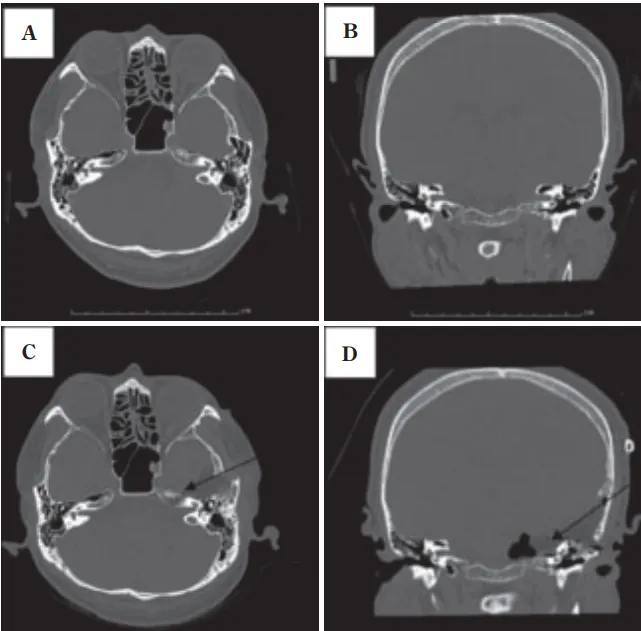

(图1)根据影像学检查结果诊断为听神经瘤,术前头部计算机断层扫描血管造影(CTA)观察到在内耳道壁后方形成的颈静脉球(带骨图像)。

图3A&B:术前轴向和冠状面计算机断层扫描图像,显示岩骨水平的内听道。一个巨大的高颈静脉球延伸到后颅窝;C&D:术后图像显示切除的内耳道前壁和上壁。